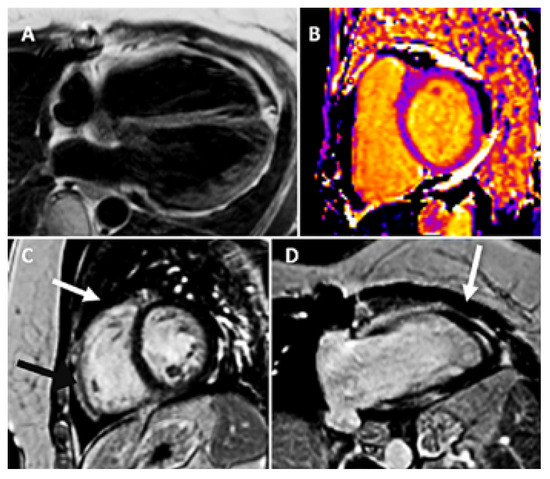

Cardiac magnetic resonance imaging (CMR) with cine, flow and tissue characterisation sequences excluded any disease of the parietal or visceral pericardium, right ventricular wall anomalies, myocardial oedema or relevant late gadolinium enhancement (Figure 3 and Figure 4), but confirmed a mild circular pericardial effusion without evidence of pericardial haematoma or myocardial rupture. Myocardial extracellular volume by native and post-contrast T1-mapping was normal with 24%. Qp/ Qs was 0.95 calculated by aortic flow and flow across the pulmonary trunk by phase contrast flow velocity mapping. A gated coronary angio-CT did not find any coronary artery fistula or anomalous communication.

Figure 4. CMR tissue characterization. (A) T1weighted turbo spin-echo (TSE); (B) native T1mapping epicardial fat (black) and pericardial effusion (white); (C) and (D) late gadolinium T1weighted imaging pictures showing pericardial effusion (white arrow), epicardial fat (black arrow) and only non-specific myocardial enhancement (late gadolinium enhancement) of the inferior insertion point.